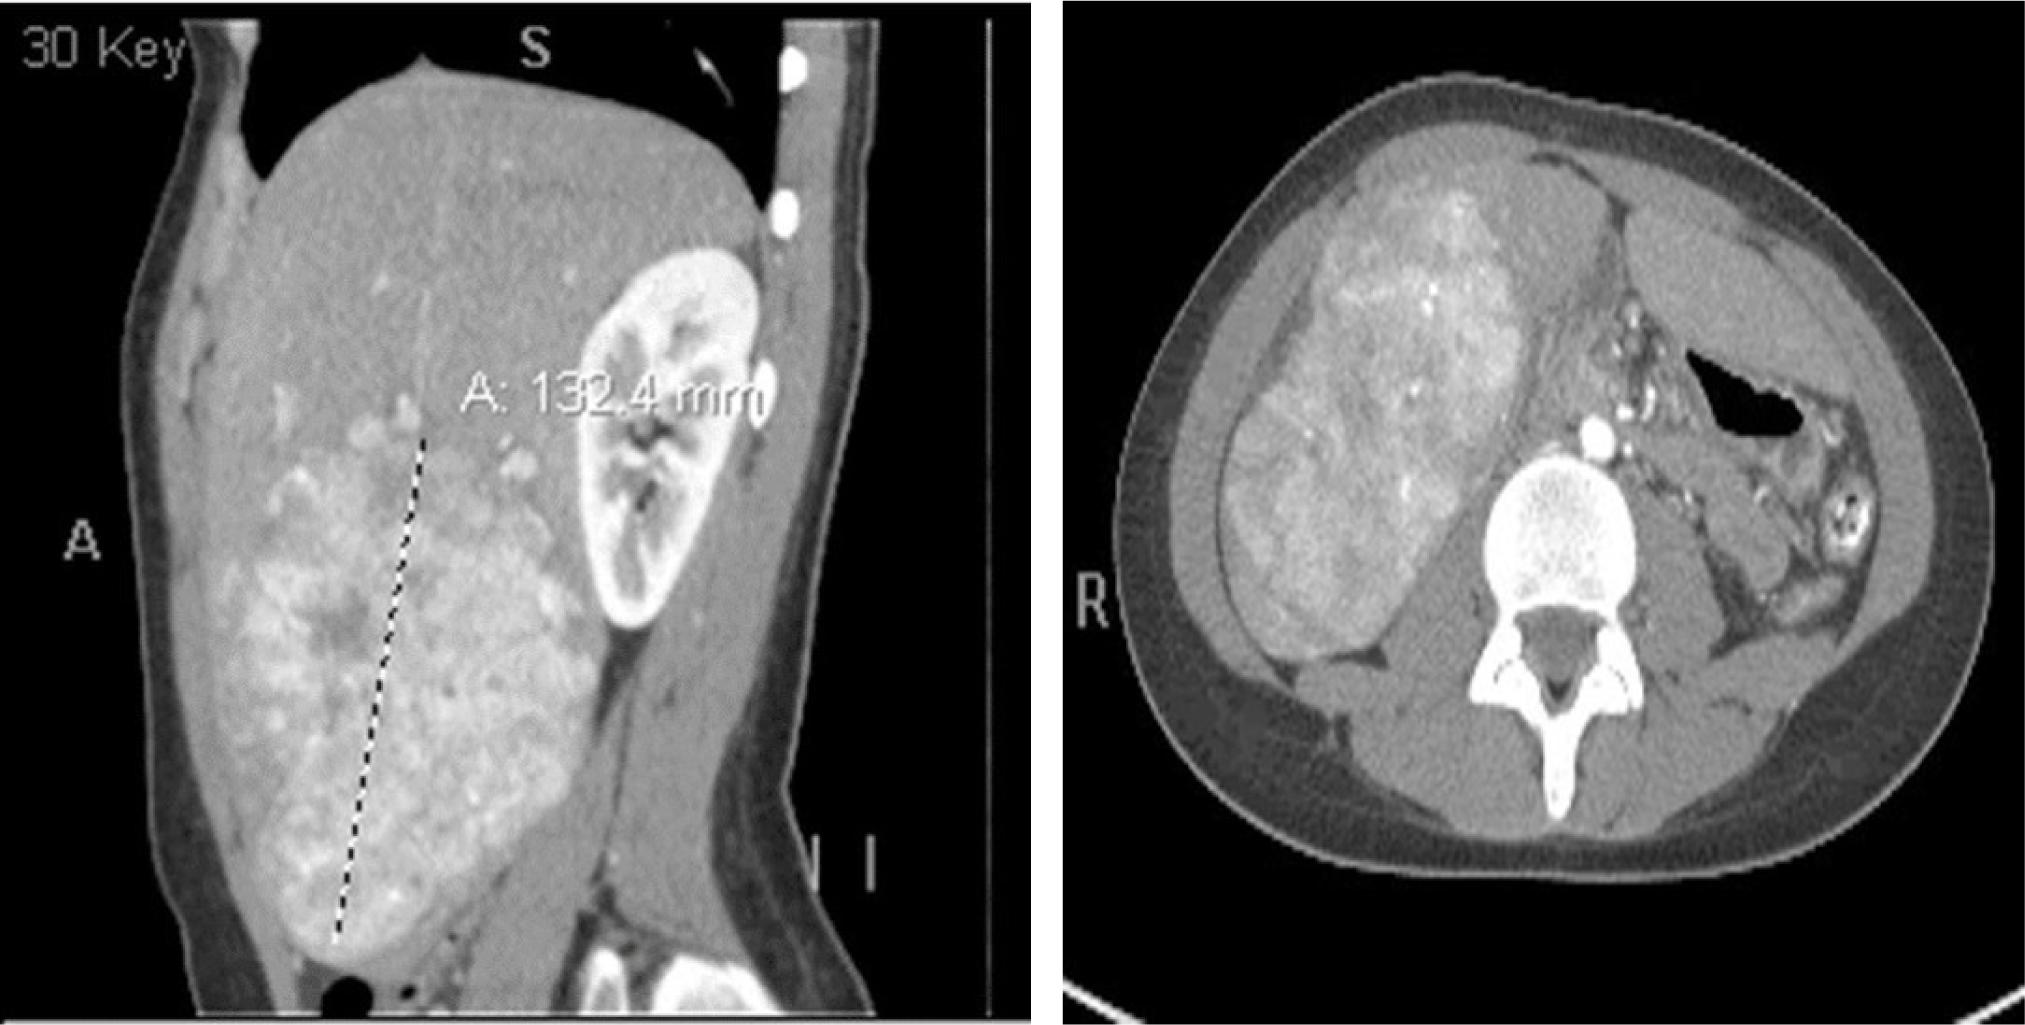

Our patient is a 16-year-old female who presented with abdominal pain for the past 8 months. She had a fever and an unintentional seven lb. weight loss. She also had tonsillar exudates, cervical lymphadenopathy, and hepatomegaly. Her monospot test was positive. CT abdomen with IV contrast shows a large (13 cm) heterogeneous appearing, highly vascular nodular right hepatic mass (Figure 1). The mass appears expansile/exophytic, and is associated with hepatomegaly. Additional smaller nodular masses were noted in liver segments 4,7, 8, and porta hepatis, which encircle the portal vein. CT chest with IV contrast reveals three distinct soft tissue nodules in the lungs concerning distant metastases of known liver mass. CA 19-9 was elevated; alpha-fetoprotein and CEA are normal. Subsequently, an IR biopsy was performed.

Figure 1: CT abdomen with IV contrast shows heterogeneous appearing, vascular nodular right mass of around 13 cm.